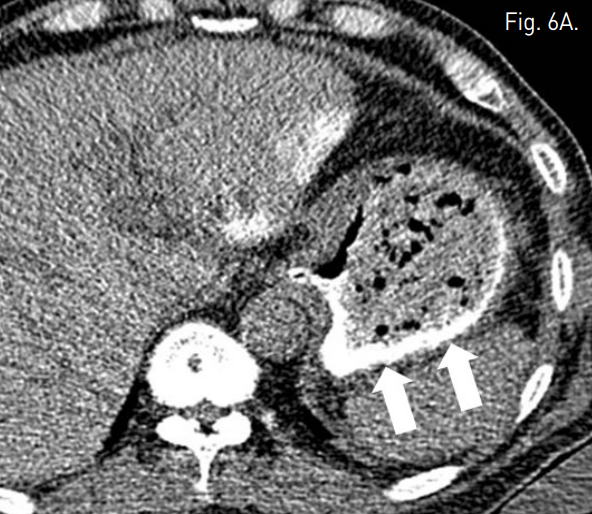

복강동맥조영술에서 비장동맥 근위부에 좌위동맥 잔류부(left gastric artery stump)가 보였으며, 그 끝에서 발생한 가성동맥류가 있다(Fig. 2). 비장동맥에 stent-graft 삽입을 위하여 우측 총대퇴동맥을 통해 8F 65cm long sheath(Teleflex, 회사, USA)를 삽입하였다. Sheath의 tip을 비장동맥 근위부까지 진입시키고 Amplatz stiff guidewire(Cook, USA)를 비장동맥 원위부까지 통과시켰다. 이후 10mm × 4cm stent-graft(S&G, Korea)의 진입을 시도하였으나 stent-graft 시스템이 비장동맥 근위부의 급격한 커브를 통과하지 못하였다(Fig. 3). 총간동맥 조영술에서 잔류위를 공급하는 부위동맥(accessory gastric artery)이나 다른 측부순환로는 보이지 않아 비장동맥 색전술을 시행할 경우 위 경색(gastric infarction)이 우려되는 상황이었으나, 수술을 담당하였던 외과의와의 상의 하에 좌위동맥 잔류부를 포함하여 비장동맥을 코일을 이용하여 색전하였다(Fig. 4). 먼저 10mm × 5cm Standard coil(Cook, USA) 2개를 이용하여 frame을 형성하고 이후 8mm × 14cm Nester coil (Cook, USA) 7개를 이용하여 색전술을 시행하였다. 코일 색전술 도중 코일의 일부가 가성동맥류로 돌출하였으나 좌위동맥 잔류부를 중심으로 비장동맥의 원위부부터 근위부까지 색전하였다. 색전술 후 상장간막동맥조영술에서 미세한 측부순환로를 통해 원위부 비장동맥이 매우 약하게 조영됨을 확인하였다(Fig. 5). 시술 후 12시간에 시행한 CT 조영증강 전영상에서 위벽에 전날 시술시 사용한 조영제가 남아 있는 소견이 보여 잔류위의 관류가 매우 저하되어 있음을 알 수 있었고(Fig. 6a) 비장의 조영증강도 매우 저하되어 있었다. 그러나 동맥기 영상에서 원위부 비장동맥은 조영이 되어 보였다. 시술 7일후 시행한 CT상에서는 위점막의 조영증강은 정상적으로 보였고, 비장에도 다발성의 작은 경색 소견이 보였으나 전반적인 조영증강은 회복된 양상이었다(Fig. 6b). 환자는 시술 52일 후 정상 식이 가능한 상태로 퇴원하였다.

Fig. 6

A. Non-enhanced CT scan performed 12 hours after embolization shows stagnation of contrast media in the stomach wall (arrows).